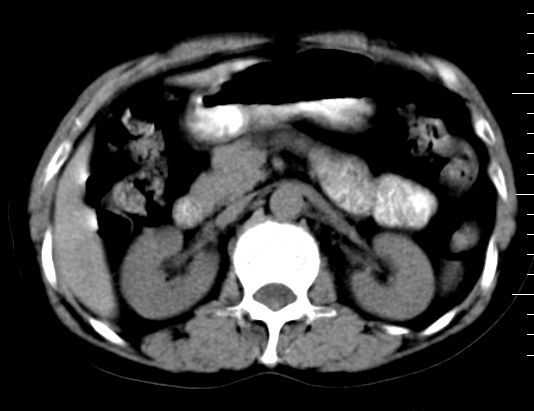

标题: CT10752:F,52岁,反复上腹部疼痛,平扫+增强. [打印本页]

f、52岁,反复上腹部疼痛2年。肺结核病史10多年,胸片双上肺结核纤维化。

ct表现:

肝大小形态未见异常,肝内外胆管无扩张,肝s8段见一动脉期明显血管样强化结节,门脉期呈高密度,延迟期呈等密度,胆囊不大,增强扫描见胆囊及胆囊颈管壁增厚,有强化。

双肾灌注良好,代谢增快,动脉期肾盂见造影剂,左肾下极背侧见一略低密度病灶,延迟期见似不强化囊肿,双侧肾上腺未见异常。

胰腺及脾未见异常。肾门水平腹膜后见小淋巴结。腹腔未见积液征象。

诊断:

1、胆囊炎(轻度)。

2、肝s8段结节,考虑小血管瘤。

3、左肾下极低密度灶,考虑囊肿可能性大,建议随访,除外小肾癌(无强化可以基本除外)。

4、目前ct表现尚不能解释患者上腹部疼痛,建议上消造影检查,除外胃炎等疾患。